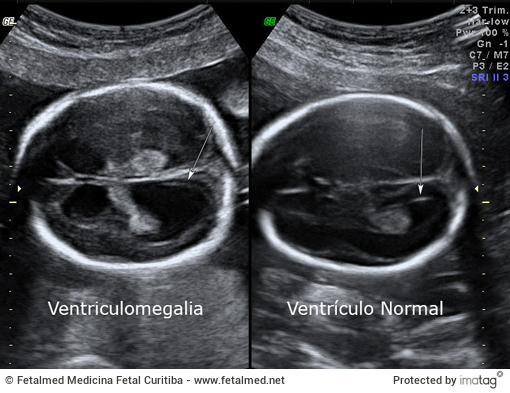

A ventriculomegalia é definida como a dilatação dos ventrículos cerebrais fetais e é um achado relativamente comum na ultrassonografia pré-natal. O objetivo deste documento é revisar o diagnóstico, avaliação e a conduta em casos de ventriculomegalia fetal leve.

Quando o alargamento dos ventrículos laterais (≥ 10 mm) é identificado, uma avaliação completa deve ser realizada. Além da dilatação ventricular o plexo coróide fica “pendente” (veja também cisto de plexo coróide). Dessa forma deve-se realizar avaliação ultrassonográfica detalhada da anatomia fetal, amniocentese para cariótipo, além de uma investigação para infecções fetais. Em alguns casos é importante também o exame de microarray (teste genético mais apurado).

Exames de ultrassonografia seriada para acompanhamento devem ser realizados para avaliar a progressão da dilatação ventricular. Algumas alterações como a holoprosencefalia também podem ser confundidas com Ventriculomegalia e por isso a avaliação por especialista é essencial. No cenário de ventriculomegalia isolada de 10 a 12 mm, a probabilidade de sobrevivência com neurodesenvolvimento normal é mais 90%. Com ventriculomegalia moderada (13 a 15 mm), a probabilidade de neurodesenvolvimento normal é de 75 a 93%.